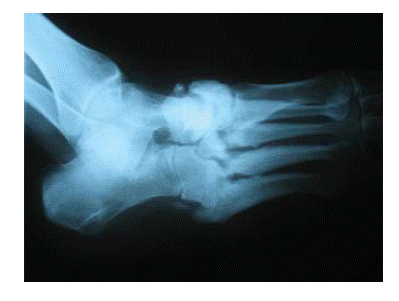

Табанның сүйек-байлам аппаратының деструктивті өзгерістері көптеген айлар бойы үдемелі дамып, айқын сүйек деформациясына әкеледі — диабеттік остеоартропатия және Шарко буынының түзілуі, бұл кездегі табанды «сүйекке толы қаппен» салыстыруға болады (7.13сурет).

7.12 сурет.Диабеттік табан синдромы кезінде дамитын Шарко буыны